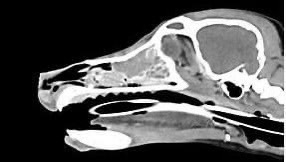

狗狗 鼻腔腫瘤 淋巴癌

鼻腔腫瘤的診斷需要仰賴電腦斷層掃瞄定位病灶處,同時使用鼻腔內視鏡探查、採樣才能確診,同時有這兩項設備的醫院並不多,所以臨床事並不是那麼容易確診。